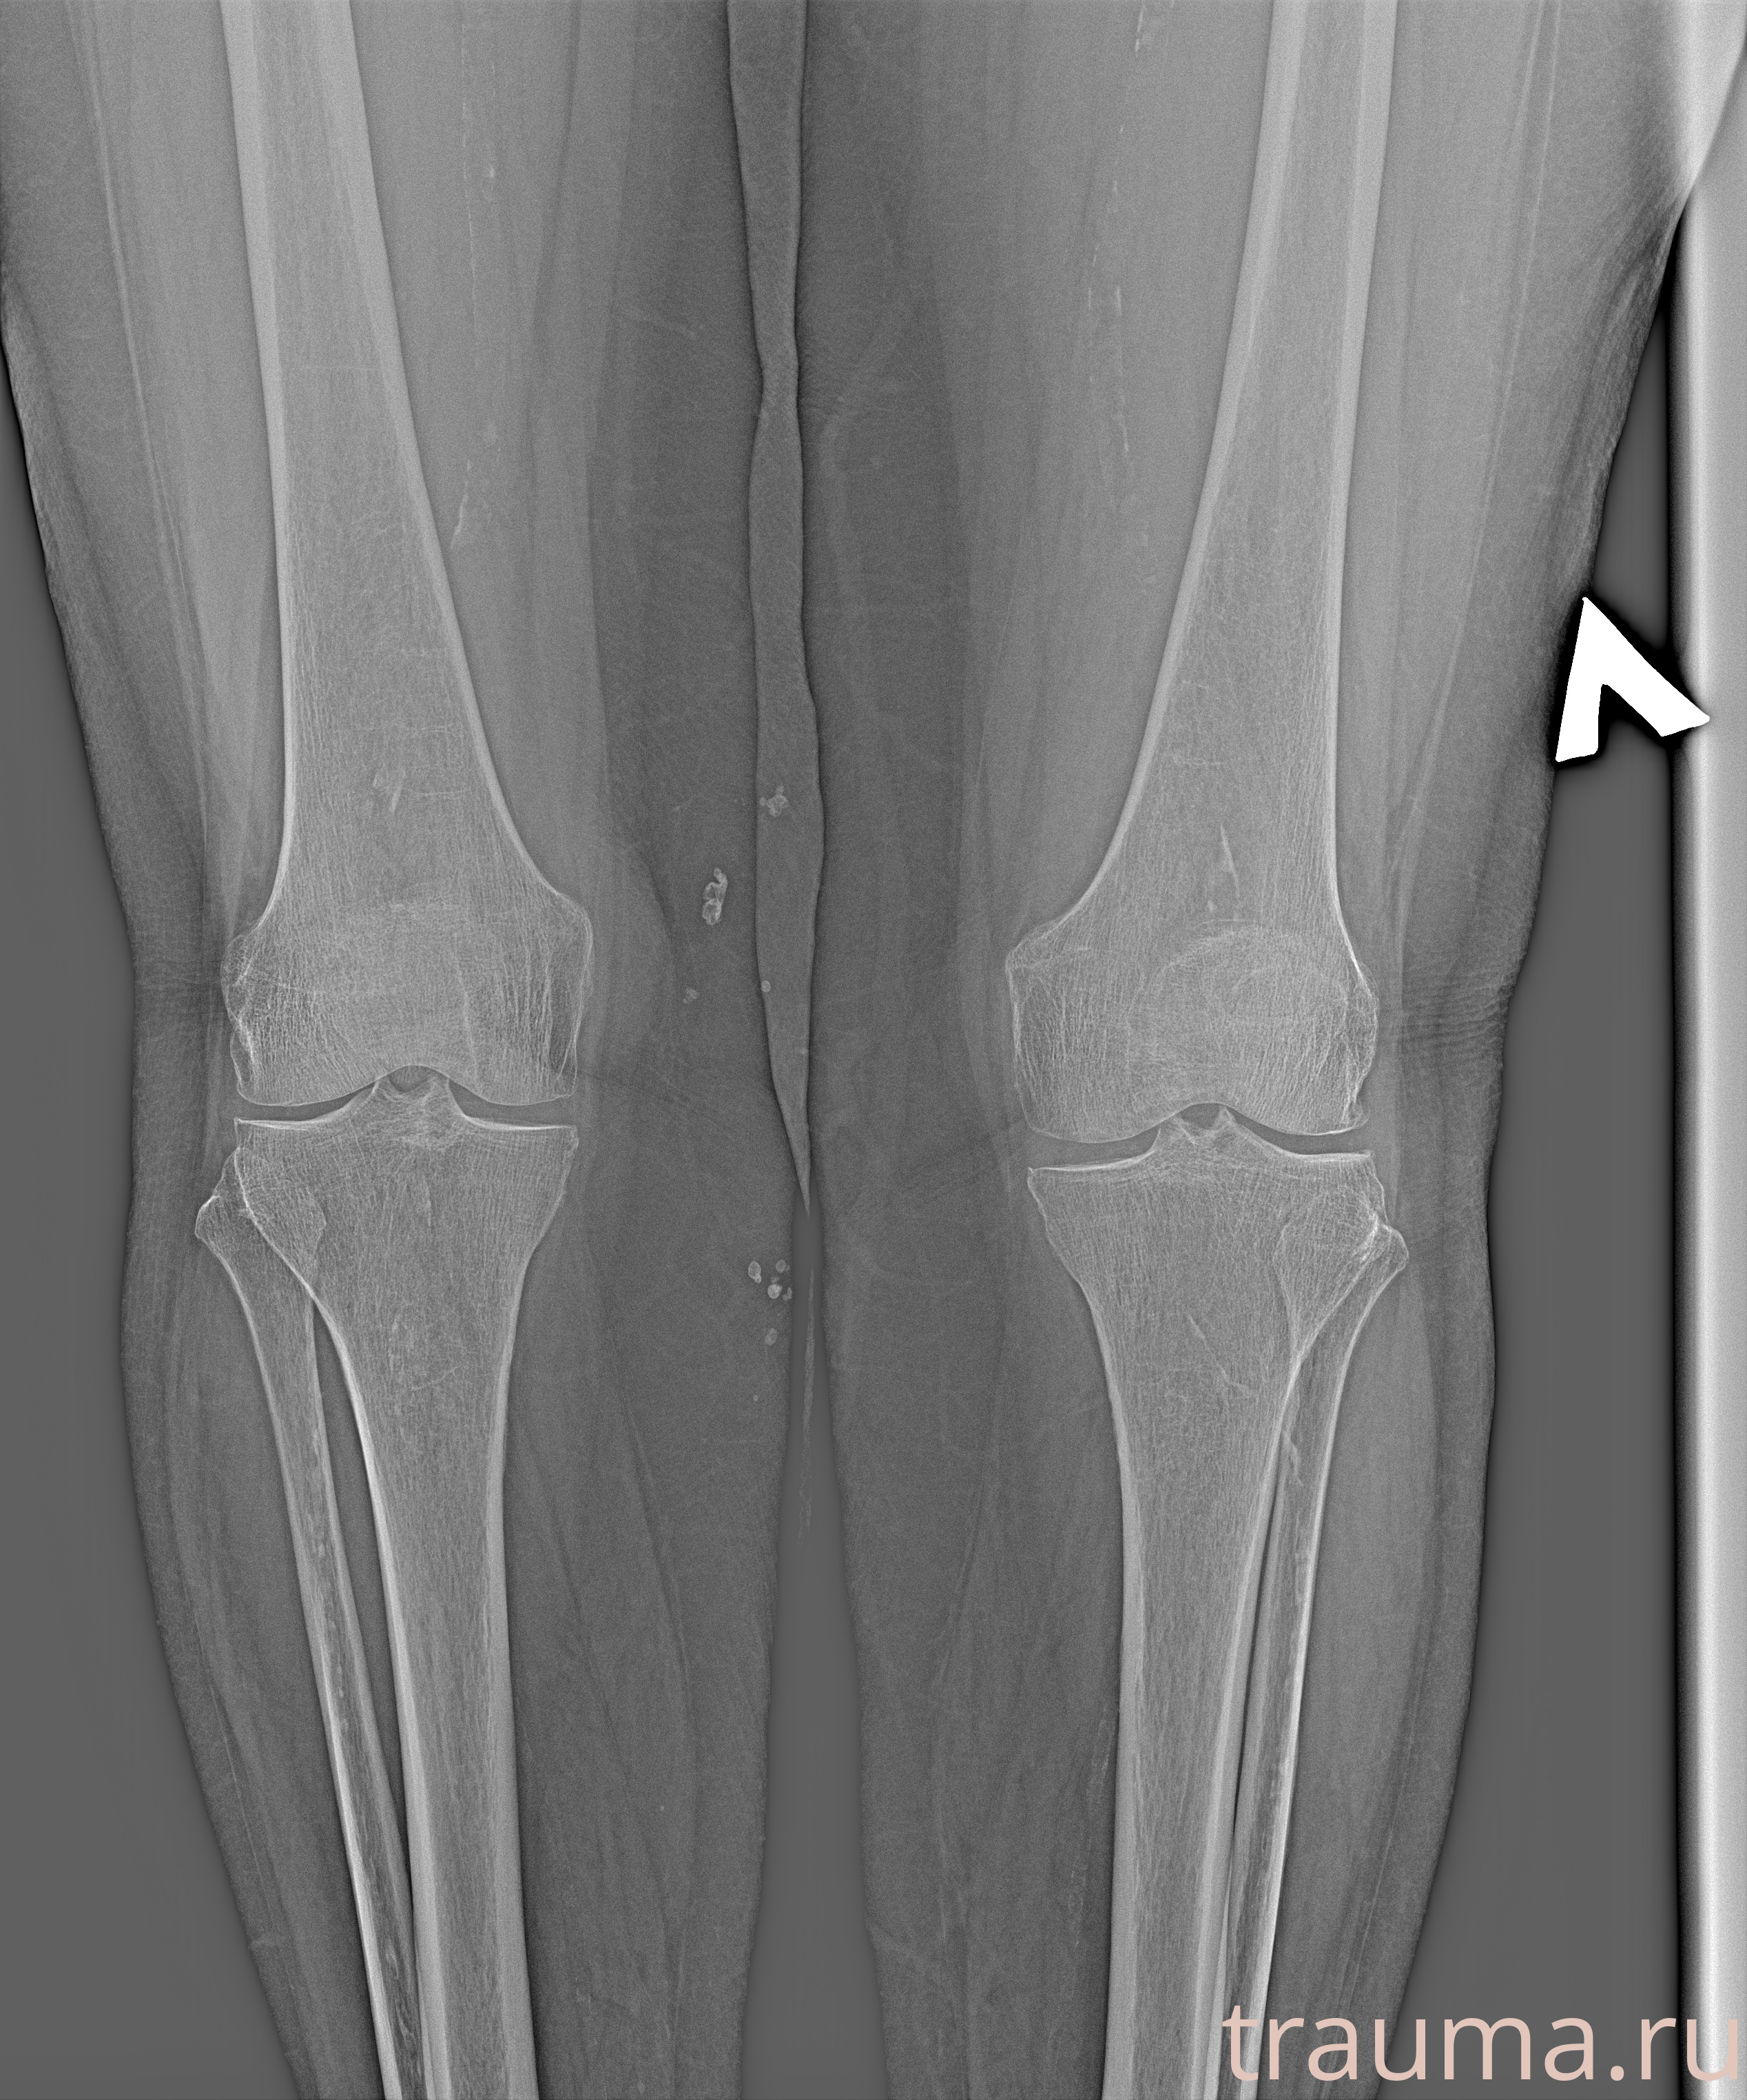

Рентгенограммы

Рентген на дому: по вашему адресу приезжает врач-рентгенолог, травматолог-ортопед с мобильным рентгеновским аппаратом, проводит диагностику травмы или заболевания, делает необходимые рентгенограммы, дает рекомендации по дальнейшему лечению. Получить качественные снимки в домашних условиях возможно благодаря уникальной методике, разработанной МосРентген Центром для института  Склифосовского